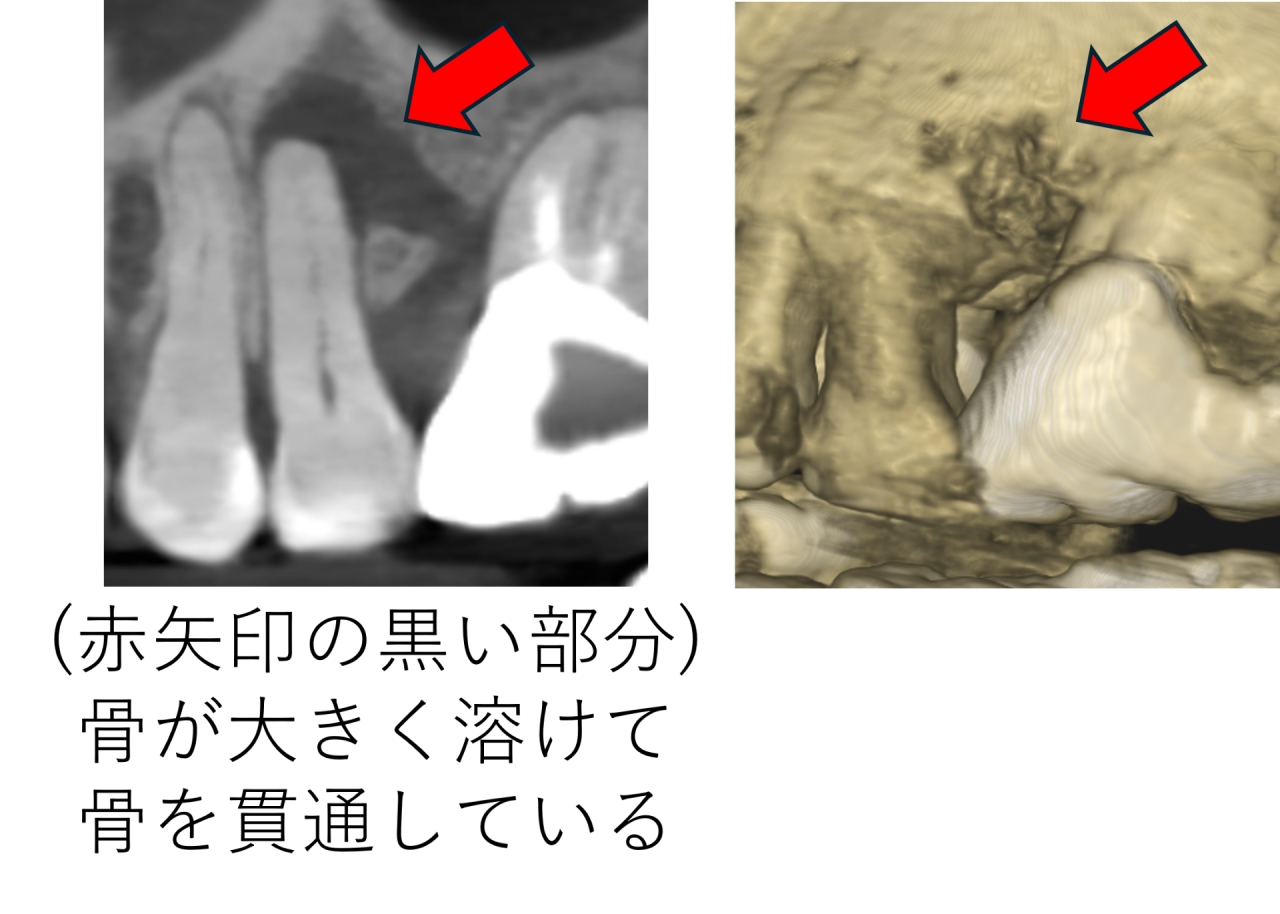

レントゲンでは、確かに根の先の骨が大きく減っていました。

黒く写る部分が広範囲に広がっている状態です。一部骨が貫通しているところもあります。

こうした所見があると、抜歯を選択するケースもあります。